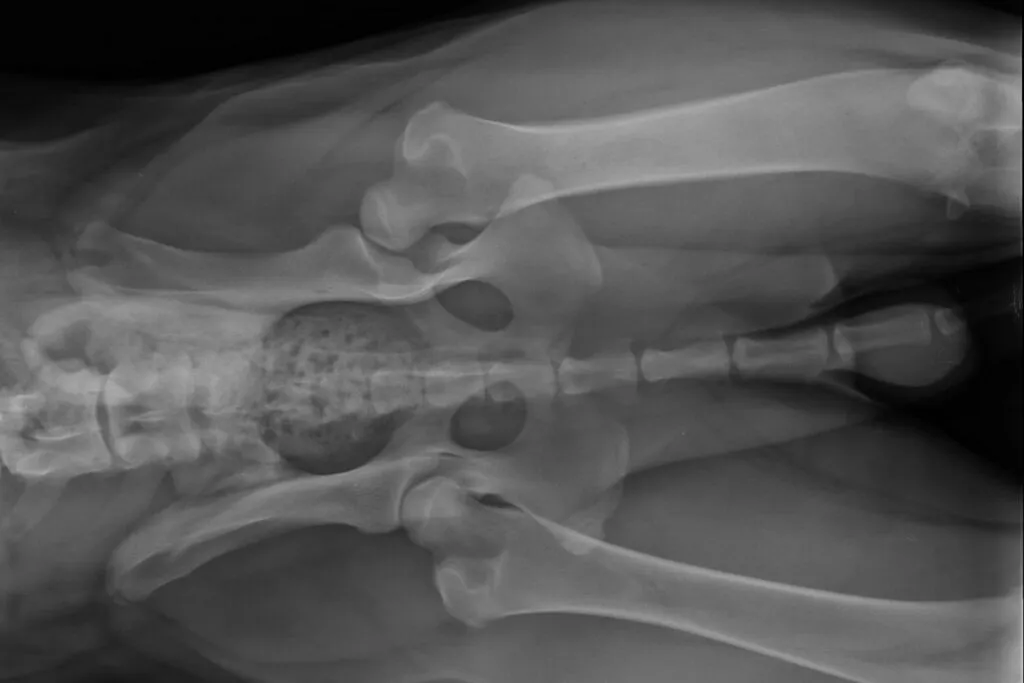

A vet diagnoses hip dysplasia in dogs using a veterinary surgeon and an X-ray examination. In order to properly assess an X-ray image of the hip joints, the HD X-ray must always be taken under sedation with the dog positioned in a standardised way. Sedation is necessary so that the dog’s muscles are relaxed and they do not feel any pain while being positioned for the image.

The vet then assesses the severity of the hip dysplasia and the changes in the hip joint based on the X-rays. A key assessment criterion is the so-called “Norberg angle”, which is determined using two lines drawn between the centres of both femoral heads and the front edge of the socket. In a dog without HD, the angle should be more than 105 degrees.

The following changes are also indicators of hip dysplasia: The hip socket, the femoral head or both are flattened. As a result, the femoral head does not sit optimally in the hip socket.

In addition, a misalignment of the femoral neck or head is often visible. There are also frequently early signs of osteoarthritis, such as bony growths on the front and rear edge of the socket and at the transition from the femoral neck to the head.

X-ray Examination for Breeding Dogs

For the selection of breeding dogs, certain criteria for taking X-rays and assessing them are required. For some dog breeds, in certain countries or for second-opinion assessments, an additional X-ray with the thighs spread and the hocks raised (“frog view”) is also required. This position makes changes to the socket edge and femur easier to see.